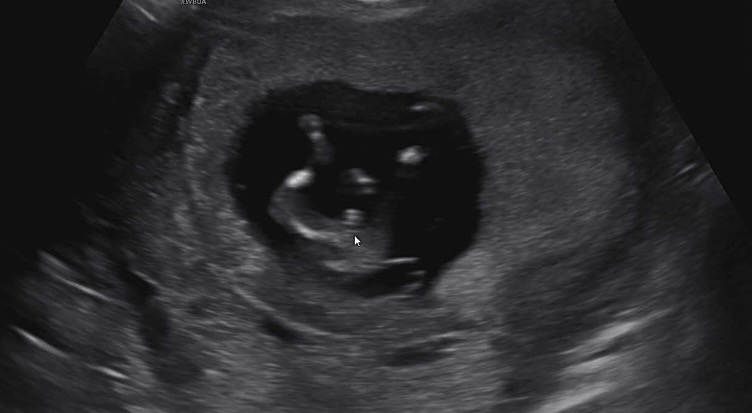

11주6일차입니다 아직 여아도 튀어나와있을 시기라는데 의사쌤은 90프로 남자아이 같다네요 여자아이길 바라고 100프로 여자일거라 확신하고 지냈던 저는 망치로 머릴 맞은거같네요.. 남아여도 건강만하다면 좋을거라 생각했지만 막상 남자 아이라 들으니 마음이...🥲🥹 슨배님들 한번 봐주세요